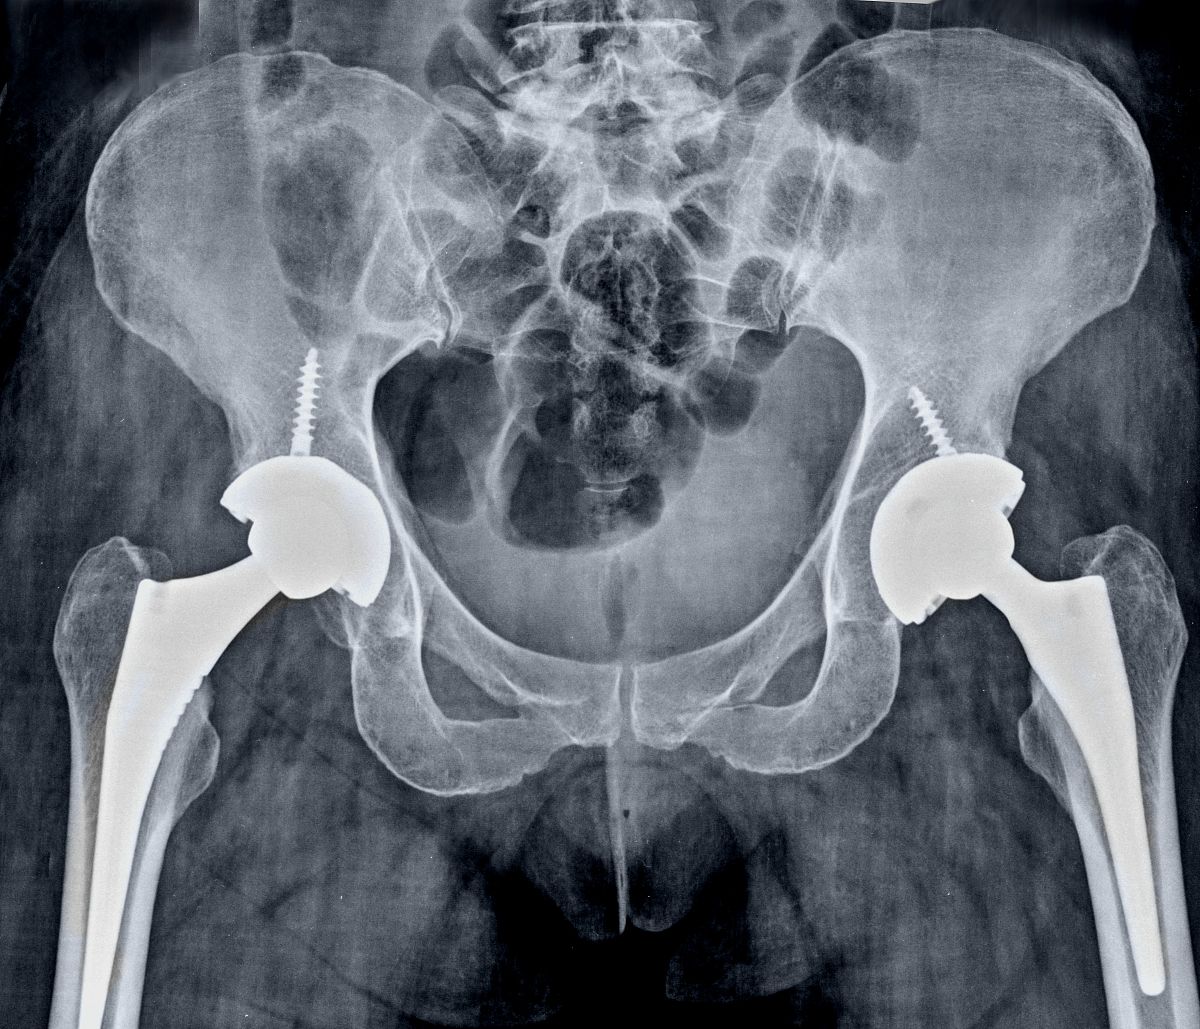

半髋关节置换手术是将患者的'髋臼'部分进行置换,用人工'髋臼'替代受损的'髋臼',同时修复或替换受损的股骨头。这种手术可以恢复患者的'髋关节'功能,减轻疼痛,并提高患者的生活质量。

然而,半髋关节置换手术也存在一些风险和限制,包括术后感染、人工关节松动等并发症的风险,以及手术适应症的限制等。因此,在决定是否进行半髋关节置换手术时,医生会综合考虑患者的年龄、全身状况、骨折类型和骨质状况等因素。